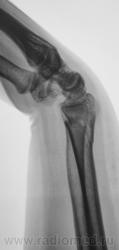

Травма.   Пациент направлен на рентгенографию лучезапястного сустава.

Вывих трапеции и гороховидной костей, ну и перелом "луча" в т.м., куда же без него.